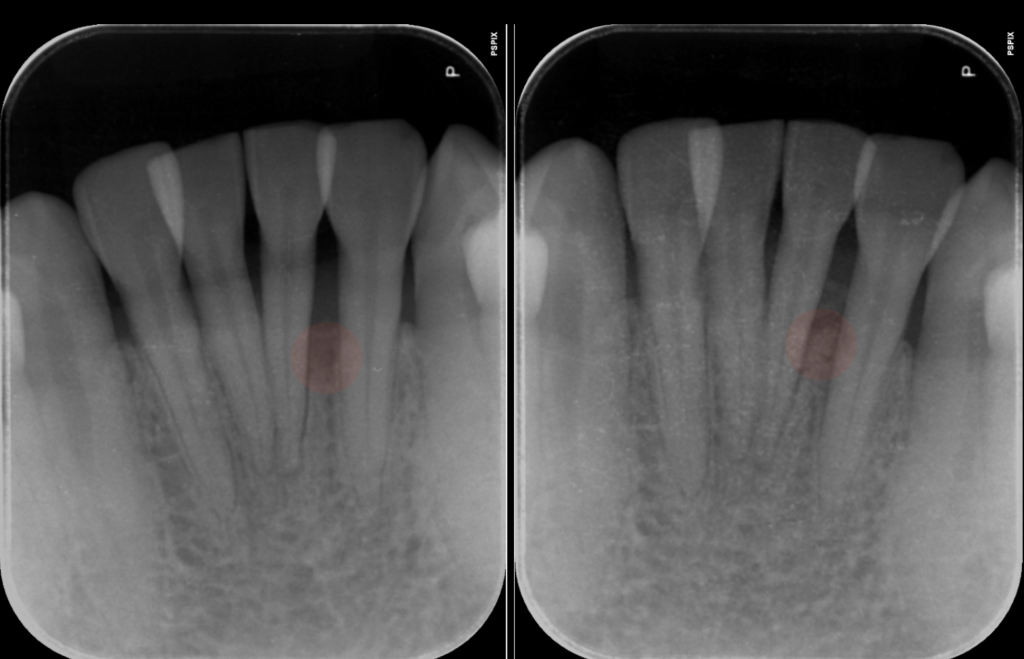

マイクロスコープとレントゲンで詳しく検査すると、

問題の歯の周囲だけ、縦に深い骨の欠損(骨吸収)があり、歯周ポケットも深い状態でした。

基本治療を行った後、改めてポケットの深さや動揺、

レントゲンで骨の状態をチェックし、

「この歯は再生療法で残せる可能性がある」と判断して、

術後の経過 ― 歯の揺れが落ち着き、骨も回復

術後は、定期的にチェックとクリーニングを続けました。

数ヶ月経過すると、

- 歯の動揺がほとんど気にならないレベルまで改善

- 歯ぐきの腫れ・出血も消失

- レントゲン上で、溶けていた骨の部分に新しい骨様の陰影が確認できるように